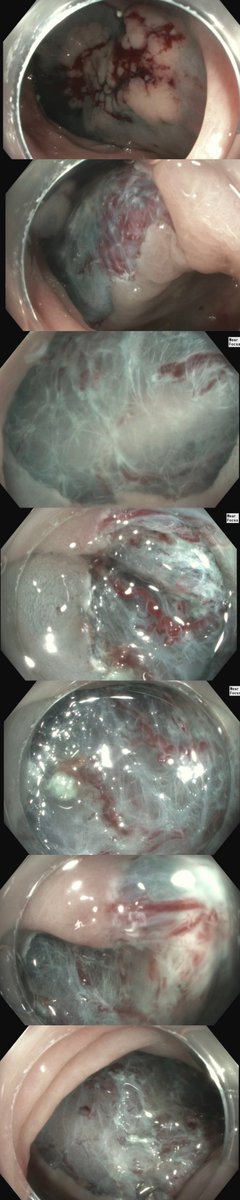

ESD ๐. 3cm BE with concerns for intramucosal ca on path removed en bloc. Excited to join @uams_GIHep and contribute to their already brilliant interventional endoscopy program @MaugarMD @SumantInamdar. Grateful to @shandrawes ๐๐ฝ๐๐ฝ๐๐ฝ @MuzaffarAkbar @Jean_Chalhoub @ASGEendoscopy